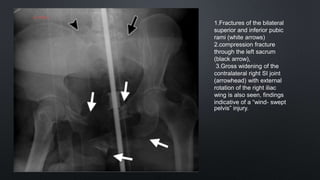

1.Fractures of the bilateral

superior and inferior pubic

rami (white arrows)

2.compression fracture

through the left sacrum

(black arrow),

3.Gross widening of the

contralateral right SI joint

(arrowhead) with external

rotation of the right iliac

wing is also seen, findings

indicative of a “wind- swept

pelvis” injury.